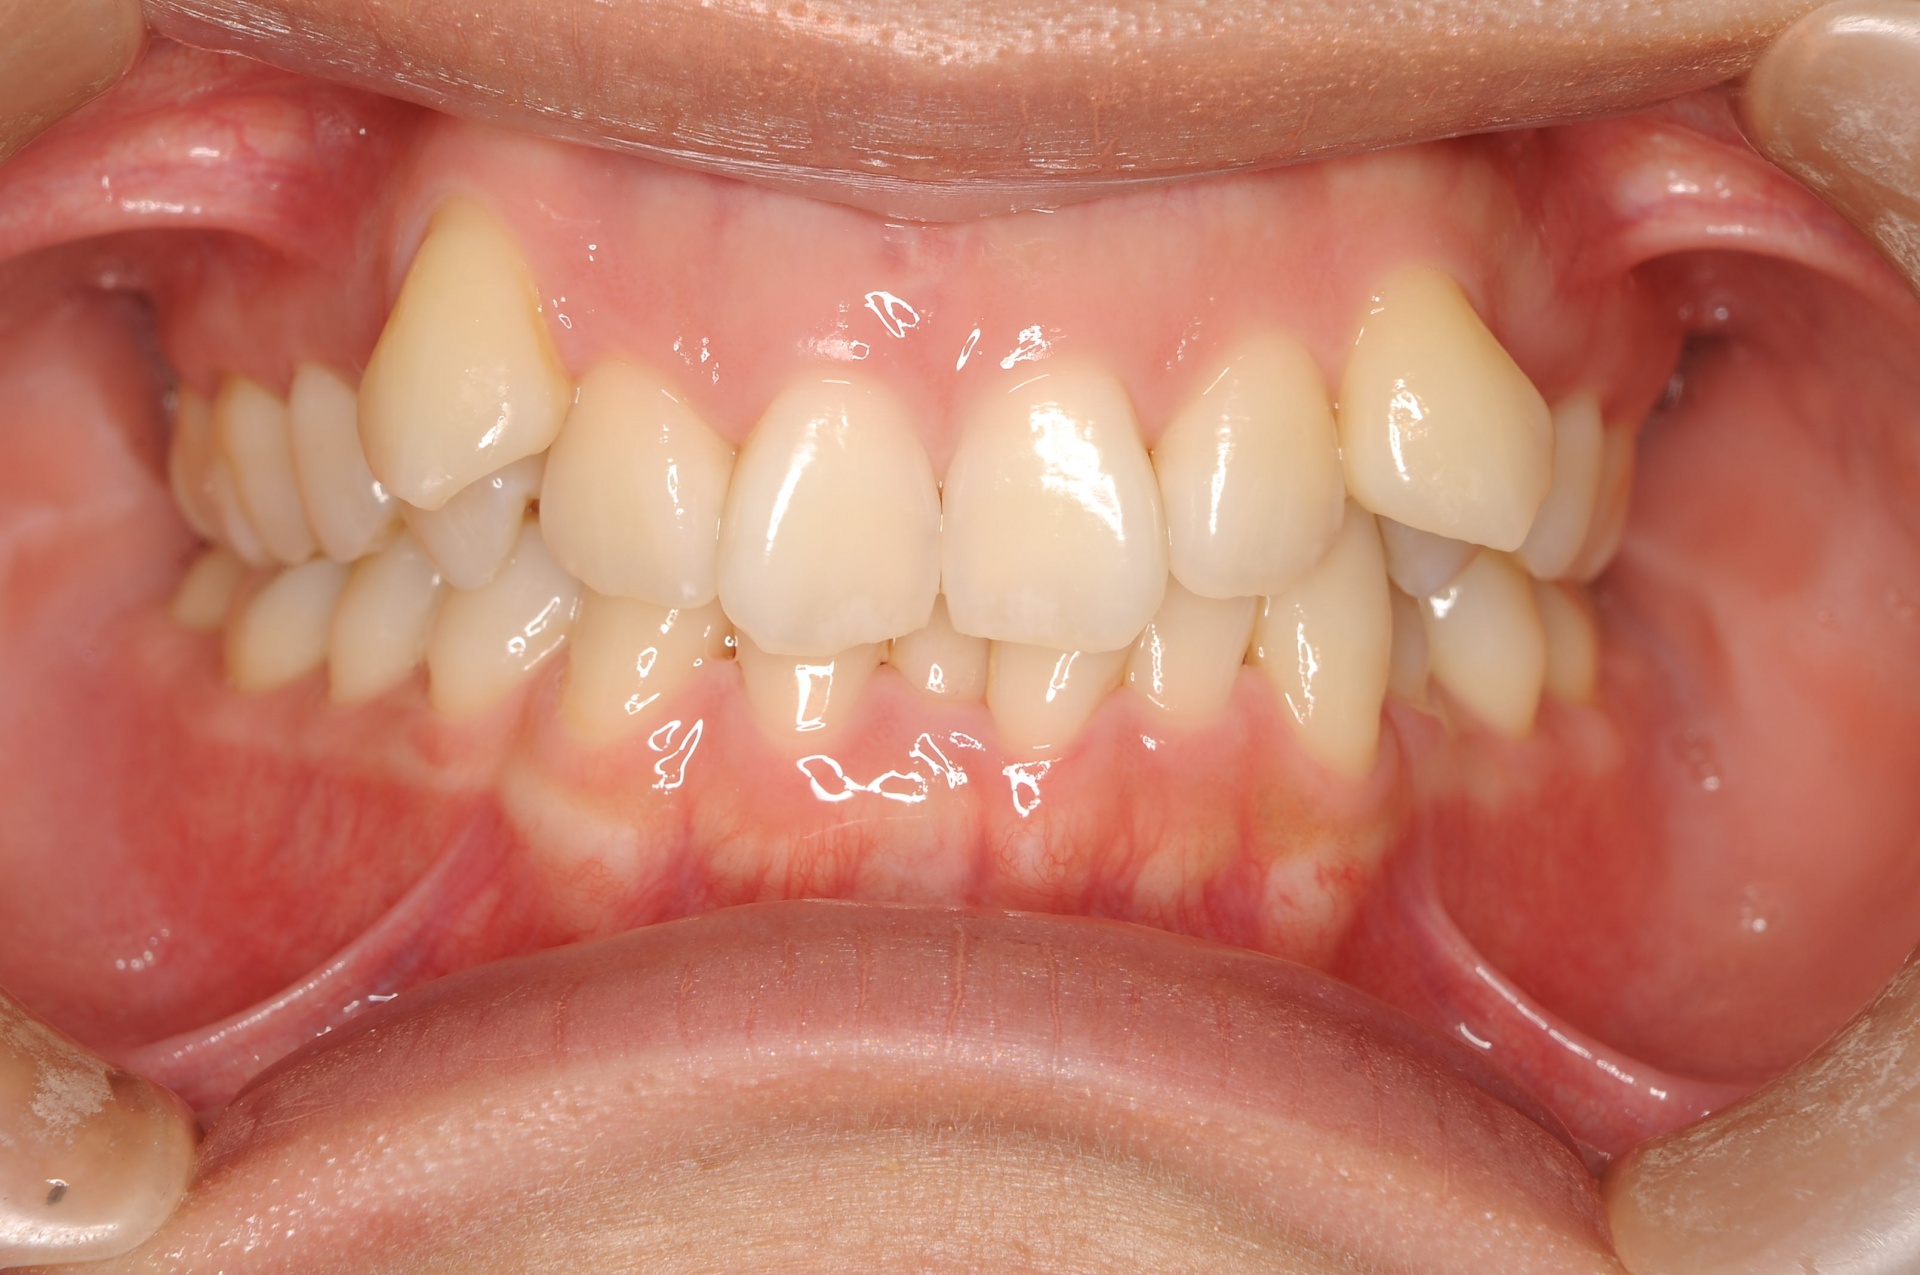

治療前

上顎両側犬歯が唇側で上方に萌出していることと、下顎前歯部の叢生を主訴に来院された20代の女性です。

治療後

上下の正中は一致し、上顎両側犬歯は歯列内に誘導されました。奥歯の咬合関係は緊密で、再配列されたことにより機能・審美ともに改善されました。